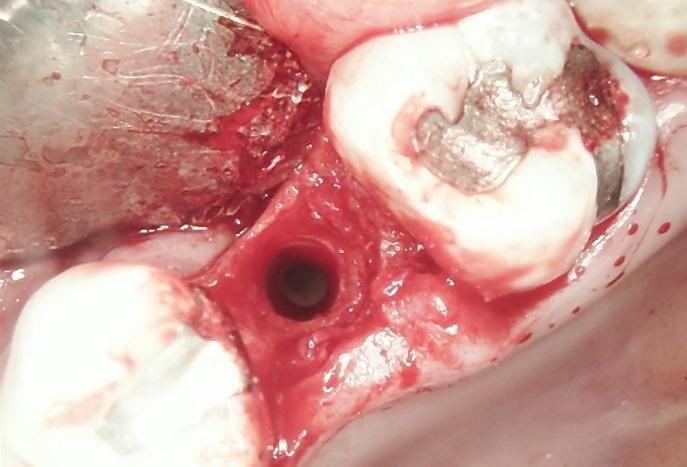

SURGERY

The failed implant was atraumatically removed, followed by thorough debridement of the surgical site.

Bone graft material was placed to restore adequate bone volume and support future implant placement.

A new implant was inserted in a prosthetically driven position, ensuring primary stability.

Surgical site was sutured to allow uneventful healing.